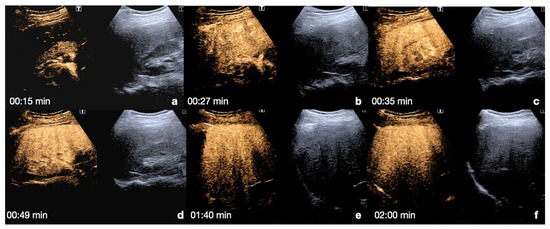

2.2.2. Follow-Up of Conservatively Managed Abdominal Trauma

In follow-up CEUS examinations, the known injured organ is targeted, and all contrastographic phases are evaluated to exclude any contained vascular lesions in the arterial phase. Any regression of the parenchymal injured area is monitored during the venous and late phases [13]. In the event of any worsening changes in the post-traumatic findings, the use of MDCT with intravenous iodinated contrast medium administration is mandatory for the same reasons as above (Figure 9).

Figure 9.

CEUS follow-up.